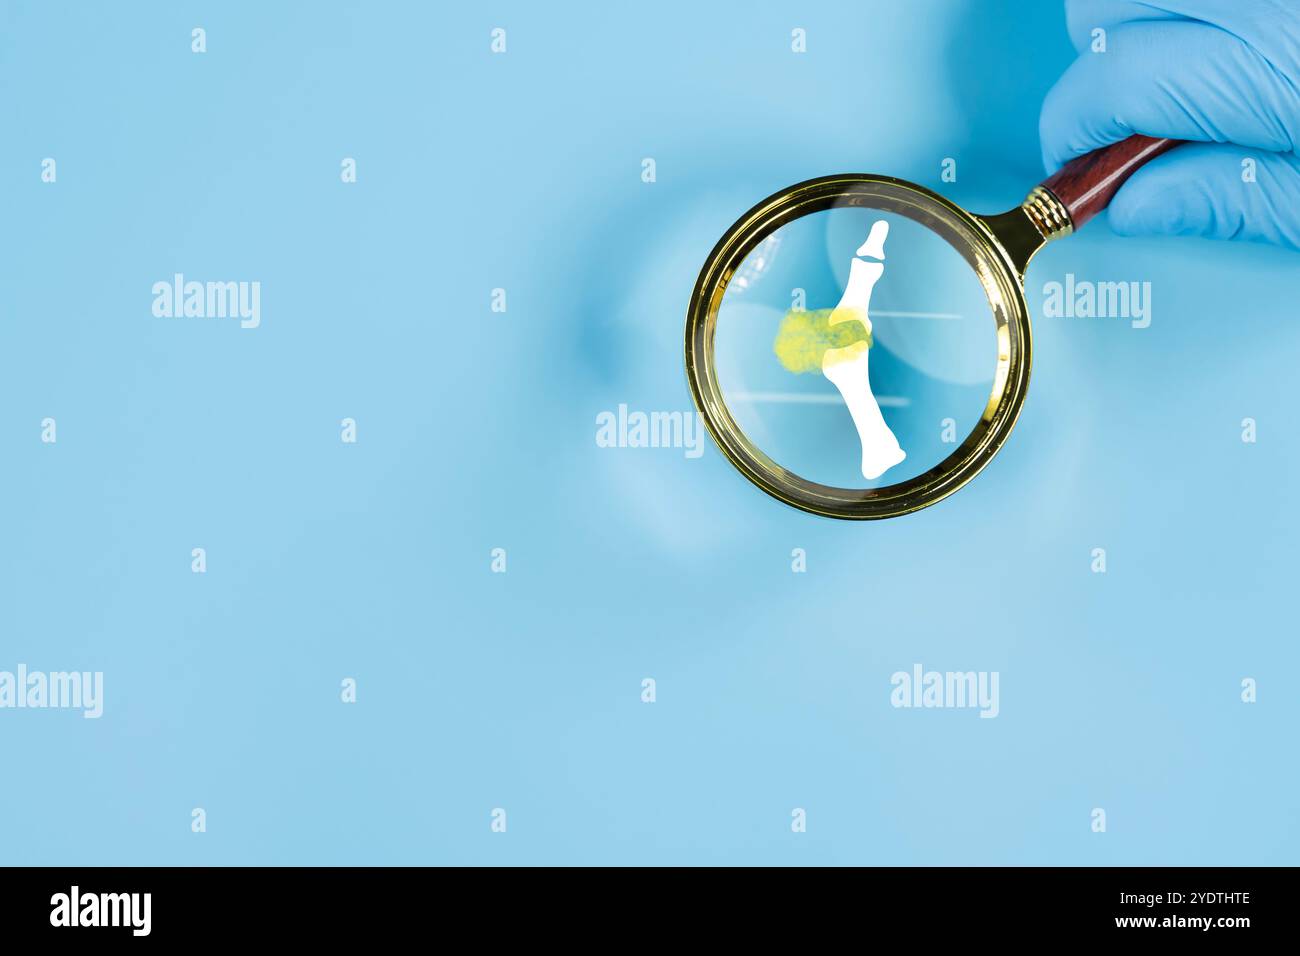

Gicht. Nahaufnahme des Gelenks mit entzündlicher Arthritis. Menschliche Fussskelettknochen durch Vergrößerungsglas isoliert, anteriore Projektion isoliert. Bildung Stockfotohttps://www.alamy.de/image-license-details/?v=1https://www.alamy.de/gicht-nahaufnahme-des-gelenks-mit-entzundlicher-arthritis-menschliche-fussskelettknochen-durch-vergrosserungsglas-isoliert-anteriore-projektion-isoliert-bildung-image628104638.html

Gicht. Nahaufnahme des Gelenks mit entzündlicher Arthritis. Menschliche Fussskelettknochen durch Vergrößerungsglas isoliert, anteriore Projektion isoliert. Bildung Stockfotohttps://www.alamy.de/image-license-details/?v=1https://www.alamy.de/gicht-nahaufnahme-des-gelenks-mit-entzundlicher-arthritis-menschliche-fussskelettknochen-durch-vergrosserungsglas-isoliert-anteriore-projektion-isoliert-bildung-image628104638.htmlRF2YDTHTE–Gicht. Nahaufnahme des Gelenks mit entzündlicher Arthritis. Menschliche Fussskelettknochen durch Vergrößerungsglas isoliert, anteriore Projektion isoliert. Bildung